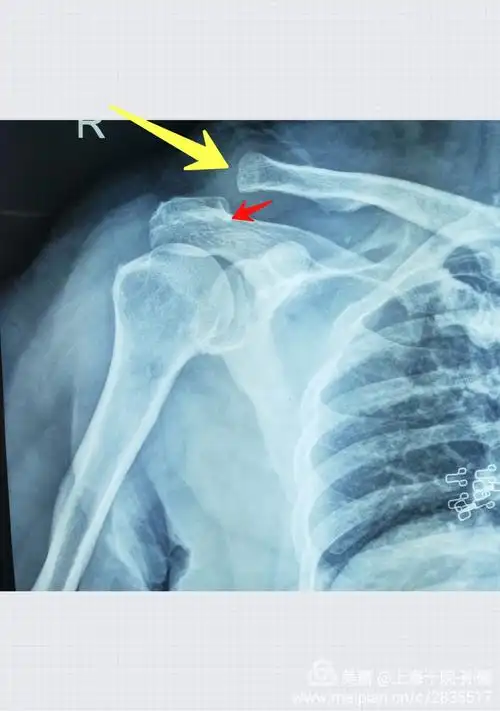

特殊体位的x光片可见肩峰前外侧明显的骨赘增生.

74疼痛弧试验:在肩外展60—120°范围内时,因冈上肌腱与肩峰下摩擦